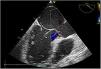

Los aneurismas del seno de Valsalva son una anomalía congénita rara, más frecuentes en varones, y habitualmente detectados en la edad adulta. Permanecen asintomáticos durante muchos años, y presentan alto riesgo de complicaciones como endocarditis infecciosa o rotura del aneurisma con comunicación a cavidades cardiacas y desarrollo de insuficiencia cardiaca aguda. Se presenta el caso de un varón de 69 años, con antecedentes de ictus hemorrágico por rotura de aneurisma cerebral 10 años antes, que ingresó por insuficiencia cardiaca en situación de edema agudo de pulmón. El electrocardiograma mostró ritmo de fibrilación auricular con respuesta ventricular a 140lpm. Se realizó cardioversión eléctrica con éxito y se inició tratamiento deplectivo con excelente respuesta clínica. Se realizó ecocardiografía transtorácica y transesofágica que mostró regurgitación aórtica leve y dilatación aneurismática del seno de Valsalva no coronariano de 5,7×4,3cm (fig. 1) que protruía y ocupaba la mayor parte de la aurícula izquierda condicionando la obstrucción al flujo transmitral (fig. 2), con el resto de aorta proximal normal. Se completó el estudio mediante una angiografía por tomografía computarizada, que mostró una placa mixta de predominio cálcico a nivel de la descendente anterior media que no causaba estenosis significativa, y confirmó la dilatación aneurismática aislada del seno no coronariano (fig. 3). Ante estos hallazgos se decidió tratamiento quirúrgico, y se realizó técnica de preservación valvular mediante sustitución de aorta supracoronaria y plastia del seno de Valsalva no coronariano. El posoperatorio transcurrió sin complicaciones.